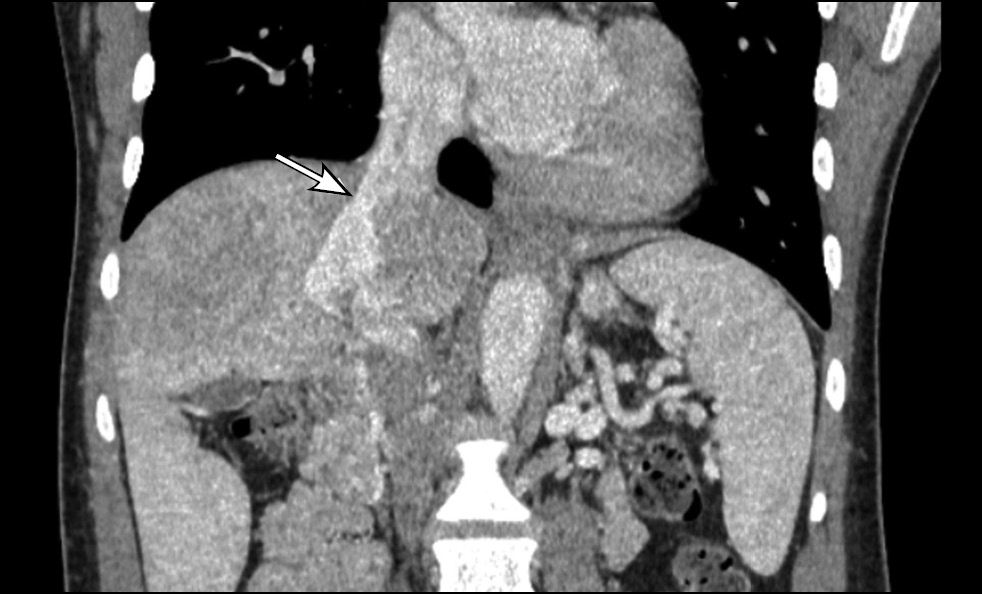

Contrast-enhanced abdominal computed tomography (CT) with multiplanar reconstruction revealed that the splenic (12 mm in diameter (Figure 1)) and superior mesenteric veins fused together, forming a portal vein conduit dilated to 28 mm in diameter (Figures 2 and 3), flowing directly into the inferior vena cava (IVC), bypassing the porta hepatis (Figure 4). Moreover, moderate liver and spleen enlargement and weak heterogeneous contrast enhancement of the liver parenchyma were noted. The findings were consistent with Abernethy malformation type Ib.

Fig. 2. Contrast-enhanced CT, portal phase, coronal view. Splenic (SV) and superior mesenteric (SMV) veins fused together, forming a portal vein conduit (white arrow).

Fig. 4. Contrast-enhanced CT, portal phase, coronal view. Portal vein conduit flowing directly into the IVC (white arrow), enlarged liver with heterogeneous parenchymal enhancement.